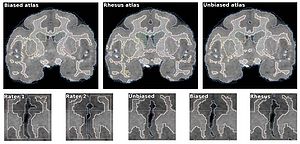

- 7.1 Atlas-guided Segmentation of Vervet Monkey Brain MRI

- 7.2 Comparison of Acute and Chronic Traumatic Brain Injury Using Semi-automatic Multimodal Segmentation of MR Volumes